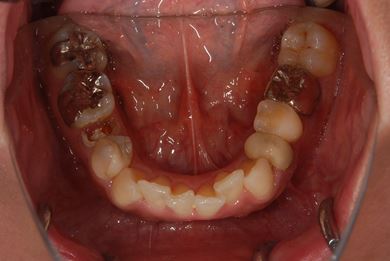

インプラントの症例写真 IMPLANT

抜歯即日スピードインプラント治療

| 性別/年齢 | 女性 / 29歳 | ||||||||||||||||||||||||||||||||

| 主訴 | 以前治療中のままだった部位の歯の根に膿が溜まって、痛みと腫れが出た。応急処置で切開して膿は取ってもらったが、根の治療がまだなので、お願いしたい。 | ||||||||||||||||||||||||||||||||

| 治療方針 | 抜歯と同時にインプラント埋入を行い、治療期間を短縮する。 | ||||||||||||||||||||||||||||||||

| 治療内容 | インプラント2本(抜歯即日スピードインプラント)、ハイブリッドセラミッククラウン3本 | ||||||||||||||||||||||||||||||||